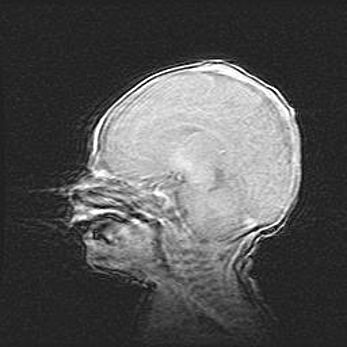

Мальформация Денди-Уокера. Киста задней черепной ямки.

Агенезия мозолистого тела.

Возраст: 2,5 месяца

Вес: 2420 г

Пол: женский

Окружность головы: 37 см

Срок гестации: 32 недели

Мальформация Денди—Уокера — редкий вид патологии ЦНС, представляющий собой врожденный порок развития каудального отдела ствола и червя мозжечка, ведущий к неполному раскрытию срединной (Мажанди) и латеральных (Лушка) апертур IV желудочка мозга. Для этогно синдрома характерна триада симптомов: гипотрофия червя мозжечка и/или полушарий мозжечка, кисты задней черепной ямки, гидроцефалия различной степени. В 70% случаев порок сочетается и с другими аномалиями головного мозга, в частности с агенезией мозолистого тела.